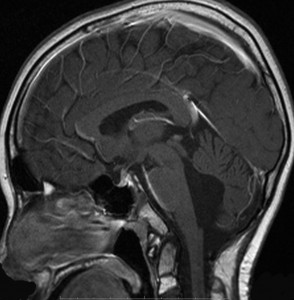

2001年,2歳1ヶ月で発症した退形成性上衣腫の男の子でした。腫瘍は第4脳室から左小脳橋角槽に伸展していましたが,全摘出しました。術後には小脳失調も無言症も脳神経麻痺もありませんでした。当時,退形成性上衣腫には脳脊髄照射が標準的治療でした。術後は何とかICE化学療法でつないで,2歳6ヶ月の時に,1日線量1.8グレイで,脳脊髄照射18グレイ,後頭窩23.4グレイ,腫瘍床12.6グレイ,腫瘍床総線量54グレイの放射線治療を行ないました。大脳と下垂体の被爆は18グレイ/10分割となります。

この画像は14歳の時のものです。大脳の萎縮は全くなく,小脳のダメージは最小限です。内分泌障害も無く甲状腺ホルモンも補充していませんが,背骨の伸びが悪いです。

5歳時 FIQ 79, VIQ 79, PIQ 85

14歳時 FIQ 75, VIQ 86, PIQ 68

神経心理学的検査からは,知能低下,記憶障害,注意障害があると診断されました。言語理解IQ 86,知覚統合IQ 71,注意記憶IQ 76,処理速度IQ 72です。全脳照射の18グレイばかりではなく,発症時の水頭症や小脳のダメージによる学習障害も加わっているのかもしれません。問題となってくるのは小学校高学年からですから,かなり長期的な観察が必要です。多くのお医者さんはせいぜい治療が終わってから自分では数年の観察しかしないので,治療を担当する先生がこのようなことを知らない可能性があります。